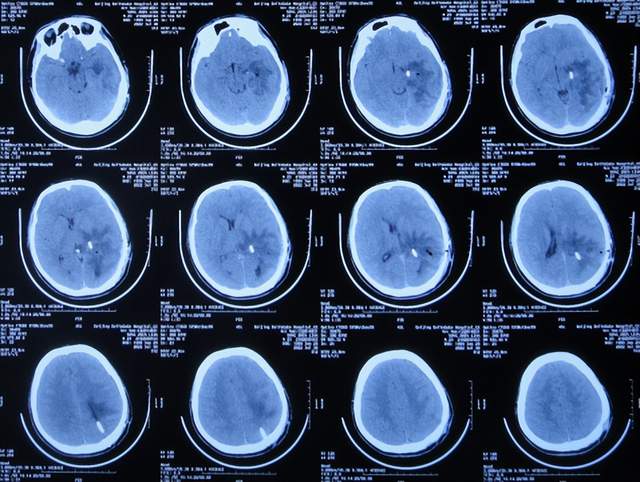

左颞角脑室腹壁外引流术后8天即2021年2月16日,查头颅CT示颞角缩小(图-16)。

图-16:2021年2月16日头颅CT

左颞角脑室腹壁外引流术后21天即2021年3月1日,查头颅CT示颞角仍有扩张(图-17)。

图-17:2021年3月1日头颅CT

左颞角脑室腹壁外引流术后23天即2021年3月3日,头颅CT增强和核磁增强示有脑脓肿(图-18、图-19)。

图-18:2021年3月3日头颅CT增强

图-19:2021年3月3日头颅核磁增强

2021年3月8日(左颞角脑室腹壁外引流术后28天),进行了脑脓肿切除术(图-20)。

图-20:2021年3月8日头颅CT

2021年3月9日(左颞角脑室腹壁外引流术后29天,脑脓肿切除术后次日),查头颅CT示脑脓肿切除术后(图-21)。

图-21:2021年3月9日头颅CT